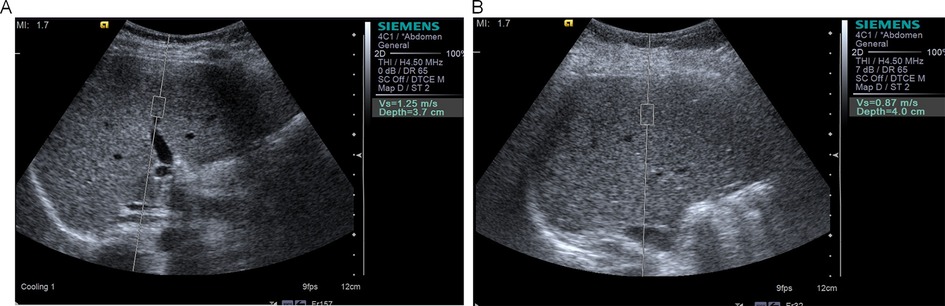

Objective: To evaluate the efficacy of a multidisciplinary clinical intervention in children with obesity by longitudinally monitoring changes in vascular elasticity and liver stiffness via ultrasound-derived parameters. Methods: A single-center longitudinal study was conducted on 120 children with obesity (aged 7–14 years, BMI ≥95th percentile). The participants underwent a 12-month intervention involving personalized low-calorie diets, structured aerobic exercise, and family-based cognitive‒behavioral therapy. Vascular parameters (carotid intima–media thickness [IMT], flow-mediated dilation [FMD], elasticity coefficient [Ep], stiffness index [β], distensibility coefficient [CD], arterial compliance [AC]) and liver stiffness (shear wave velocity [SWV]) were assessed at baseline (T0), 6 months (T1), and 12 months (T2) via Siemens S2000 ultrasound with ARFI technology. Statistical analyses included repeated-measures ANOVA, Pearson correlation, and multivariate linear regression. Results: Significant improvements were observed in FMD (7.1% to 9.5%, P<0.001), Ep (60.5 kPa to 42.3 kPa, P<0.001), β (6.25 to 4.55, P<0.001), CD (10.05 kPa to 14.9 kPa, P<0.001), AC (0.96 to 1.29 mm²/kPa, P<0.001), and SWV (1.36 m/s to 0.98 m/s, P<0.001). The carotid IMT did not significantly change (Δ=−0.01 mm, P=0.16). Multivariate regression identified ΔBMI as an independent predictor of ΔFMD (β=0.32, P=0.003) and ΔSWV (β=−0.41, P<0.001). Conclusion: Ultrasound-based multiparameter assessment effectively quantifies improvements in vascular and hepatic function following clinical intervention in children with obesity.